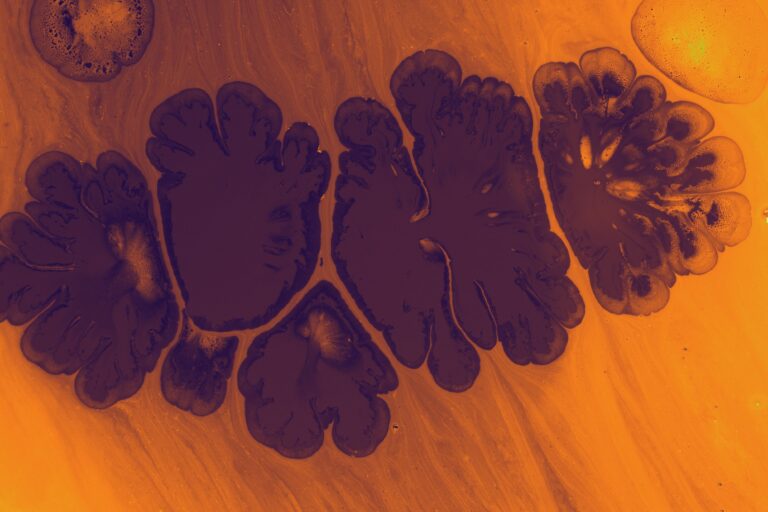

One of the most compelling pieces of evidence in this framework is the finding that in every cancer cell that has been carefully examined in its natural tissue environment, there are defects in the number, structure, and function of the mitochondria. Not in some cancers. In all of them.

A key discovery involves a molecule called cardiolipin, the signature lipid of the inner mitochondrial membrane. Cardiolipin plays a critical structural and functional role in the electron transport chain, the machinery that produces the vast majority of cellular energy through oxidative phosphorylation. In cancer cells, cardiolipin is consistently abnormal. And when cardiolipin is abnormal, the proteins of the electron transport chain cannot function properly. Energy production through normal respiration is compromised.